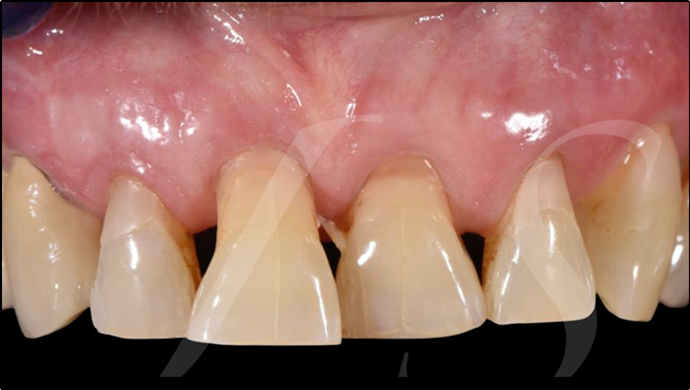

“ One implant /One tooth/ One hour step-by-step

+ associated connective graft ”

Clinical case: EImmediate implant placement & loading of #35 extraction socket with defect

- Courtesy of Dr. Kwang Bum Park, Korea -

Dr. Laurent Sers, immediate loading, digital guided surgery, digital ONE-DAY implant, maxillary anterior, #21, guided surgery, immediate loading, AnyRidge, R2GATE, Mega ISQ, R2GATE Full Surgical Kit

implant system, R2GATE Guide, R2GATE surgical kit (AnyRidge), Mega ISQ